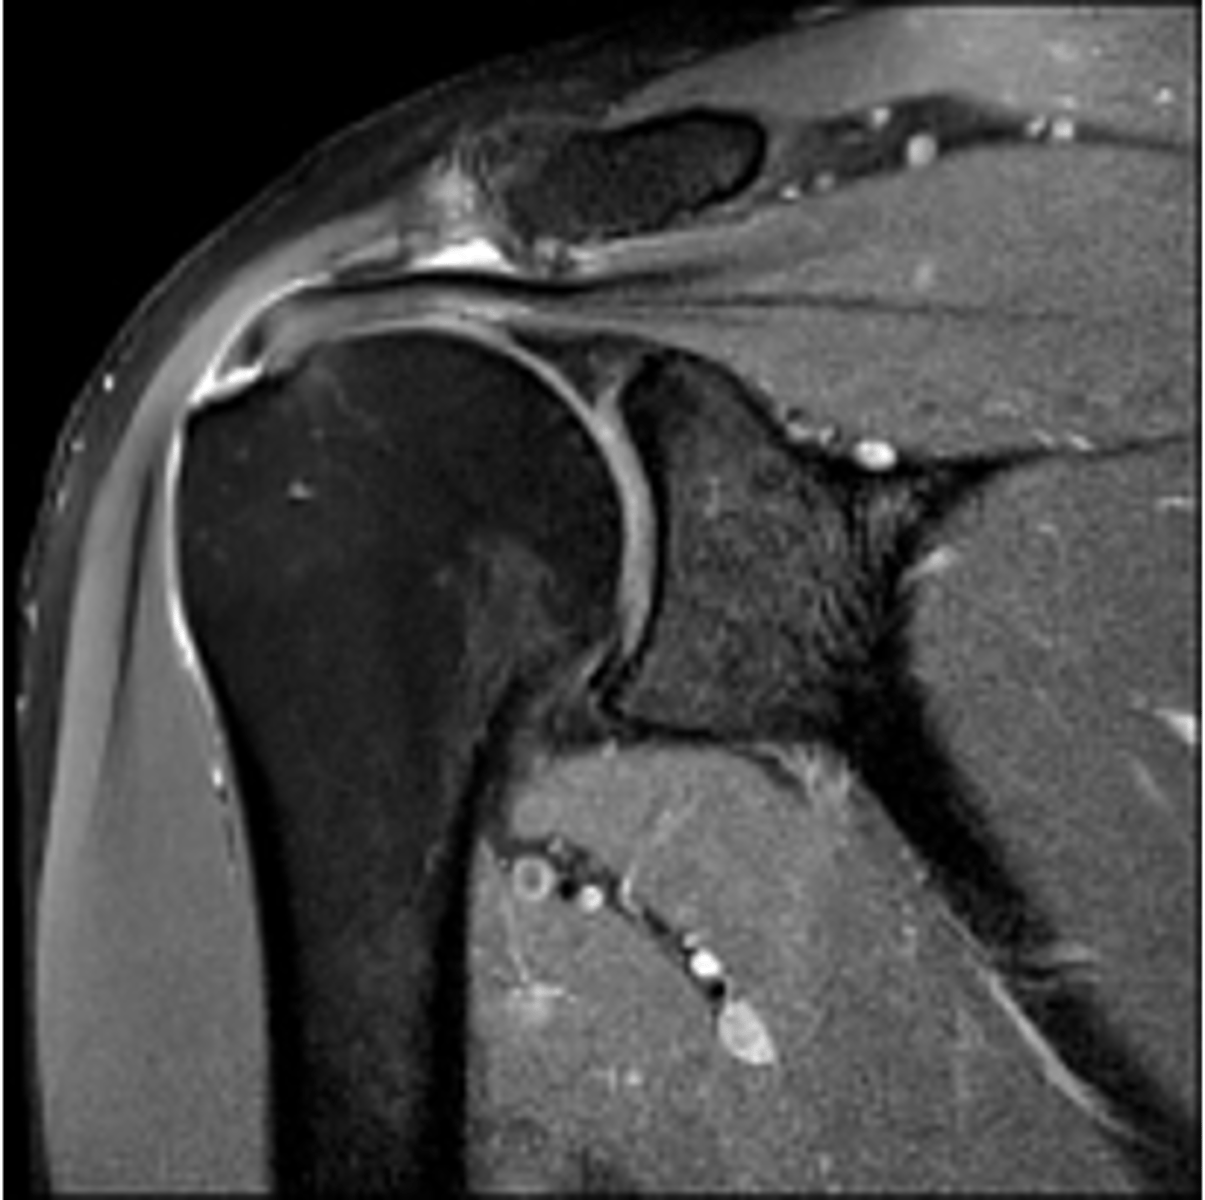

Coronal view of an AC joint separation (grade II sprain) -- an MRI allows us to see the torn ligaments, fluid accumulation, swelling, and get a good sense of the edge of the joint to see how healthy the cartilage is

What is this image depicting? Why is an MRI helpful vs. an x-ray?

Sagittal view of an AC joint separation (grade I-II) -- torn ligaments (sitting on top of the ACJ) buckle and get wavey (when they should be straight and tight normally) and inflammation is also present on the bottom side of the joint

What is this image depicting? How do you know?